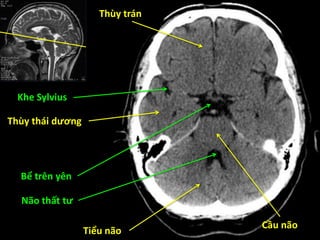

Thùy trán

Thùy đỉnh

Liềm đại não

Thùy chẩm

Đám rối mạch mạc

Thùy đảo

Não thất ba

Bể trên tiểu não

Đầu nhân đuôi

Đồi thị

Nhân bèo

Bao trong

Bèo sẫm

Cầu nhạt

Cánh tay trước

Thùy thái dương

Tiểu não

Cầu não

Não thất tư

Bể trên yên

Khe Sylvius

Hành não

Xoang chũm

Thùy trán Thùy tháidương Tiểu não Cầu não Não thất tư Bể trên yên Khe Sylvius